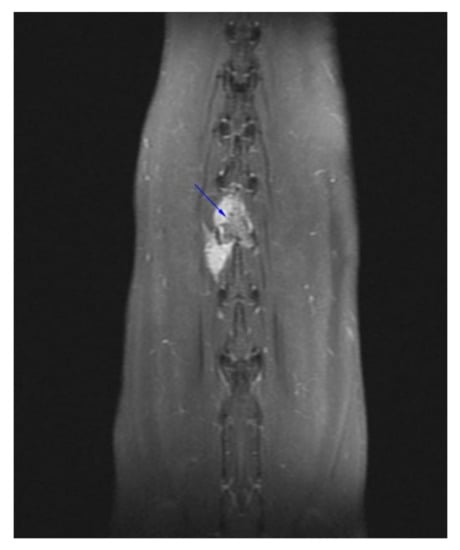

Successful Treatment of Vertebral Osteosarcoma in a Cat Using Marginal Surgical Excision and Chemotherapy

:1. Case Description

2. Materials and Methods

3. Results